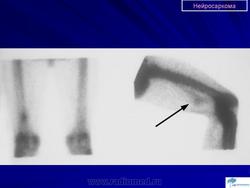

Онкология. Саркома. Нейросаркома. +

Нейросаркома.